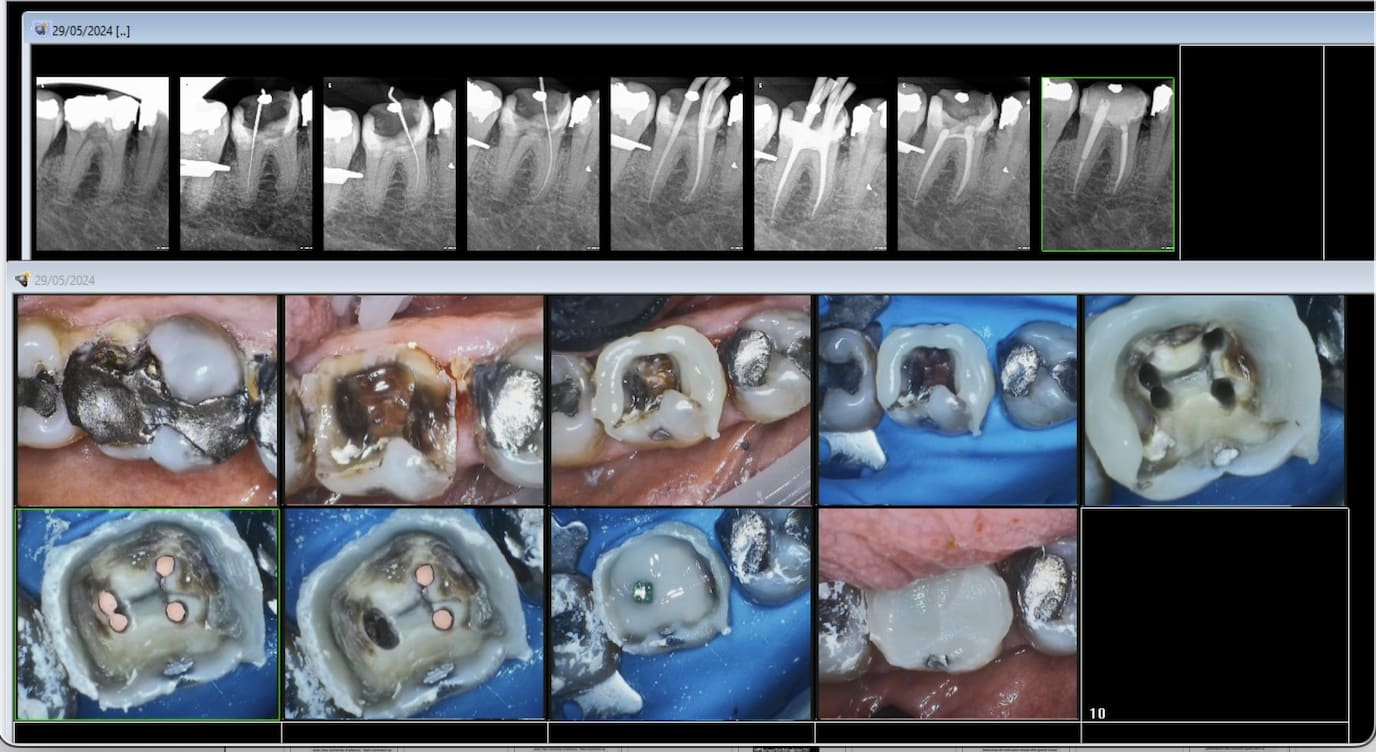

Capture d’écran 2024-06-18 à 17.24.00.png

Capture d’écran 2024-06-07 à 17.00.22.png